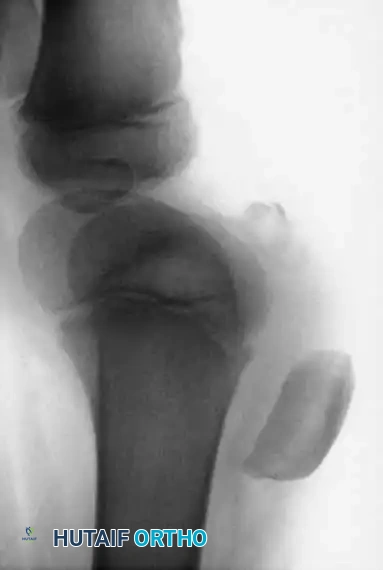

Clinical Evaluation and Blocks to Reduction

Patients present with an acute, tense hemarthrosis, severe pain, and an inability to bear weight. Aspiration of the hemarthrosis (yielding fat globules from the marrow space) provides significant pain relief and allows for a more accurate clinical examination.

Clinical Pearl: The most significant complication of a displaced tibial eminence fracture is not anterior instability, but rather a mechanical block to terminal extension. The displaced fragment impinges against the intercondylar notch of the femur.

Fractures of the tibial intercondylar eminence (tibial spine) are the pediatric equivalent of a mid-substance Anterior Cruciate Ligament (ACL) rupture. Because the pediatric ligaments are biomechanically stronger than the adjacent physeal and chondro-osseous structures, applied tensile forces result in an avulsion of the bony attachment rather than a tear of the ligament itself.

The mechanism of injury typically involves forced hyperextension of the knee, often combined with valgus or varus rotational stress—commonly seen in bicycle accidents or contact sports.